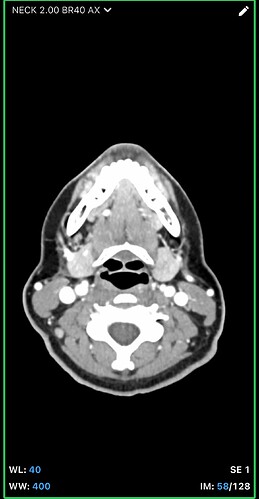

I think the best CT imaging view to look at whether your hyoid is digging into anything is by going into the axial view of your imaging. In the axial view look for the horseshoe shaped hyoid bone. I’ve attached what to look for. Take a couple screen shots and upload them and I can help interpret the imaging.

In your first & last pictures, you can see how close to your spine the greater horns of your hyoid are. Your whole hyoid looks like it’s been pushed back further in your neck than it should be possibly producing Hyoid Bone Syndrome (HBS).

@leo this is the closest one. Can you go back to your axial view and go to the very last slice that you can see the tips? I think you might be one or two frames off. I attached my imaging to help. Our hyoids might be at slightly different angles so it might not be a perfect comparison, but I think you can go up a slice or two to see the tips better. Basically follow the bone until it disappears then go back one frame to capture it.